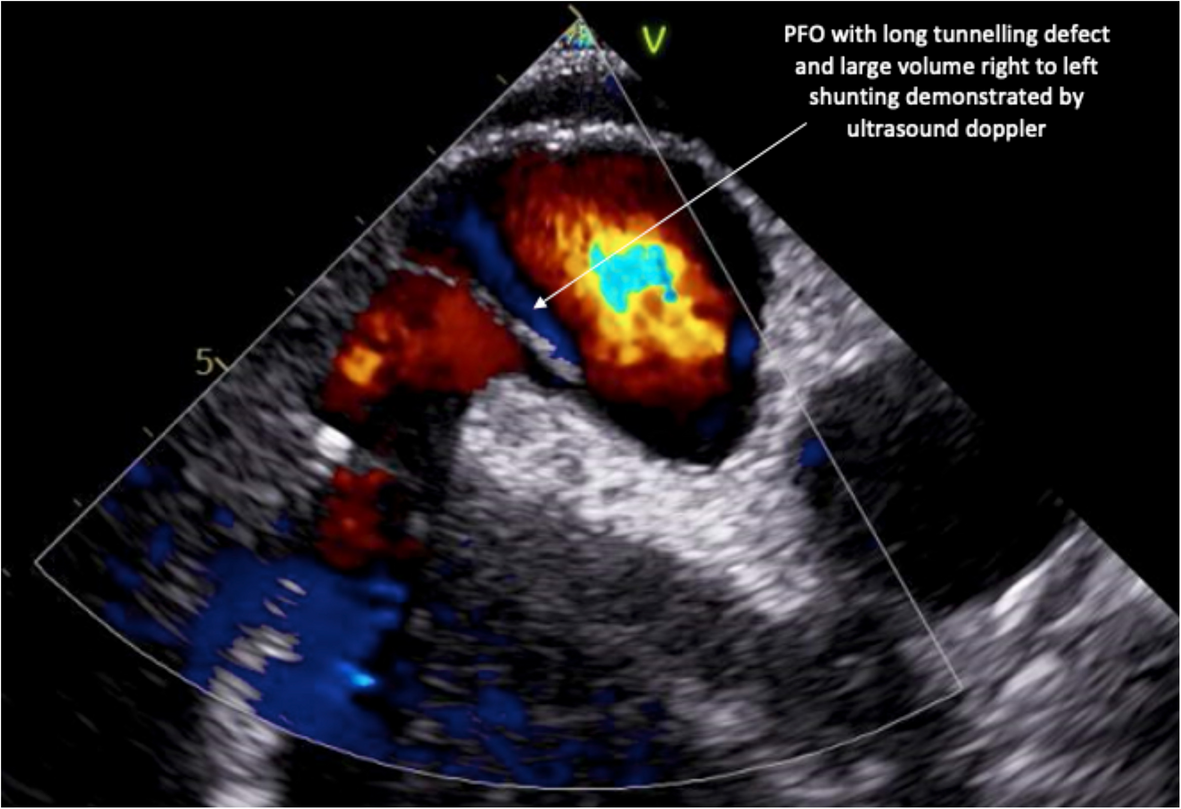

pfo shortness of breath sale